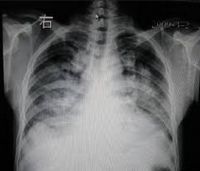

肺水肿间质期的X线表现主要为肺血管纹理模糊,增多,肺门阴影不清,肺透光度降低,肺小叶间隔增宽。两下肺肋膈角区可见与胸膜垂直横向走行的KerleyB线,偶见上肺呈弧形斜向肺门较KerleyB线长的KerleyA线。肺泡水肿主要表现为腺泡状致密阴影,呈不规则相互融合的模糊阴影,弥漫分布或局限于一侧或一叶,或从肺门两侧向外扩展逐渐变淡成典型的蝴蝶状阴影。有时可伴少量胸腔积液。但肺含量增加30%以上才可出现上述表现。CT和核磁共振成像术可定量甚至区分肺充血和肺间质水肿,但费用昂贵。

- 分布和形态呈多样性,可呈中央型、弥漫型和局限型。中央型表现为两肺中内带对称分布的大片状阴影,肺门区密度较高,形如蝶翼称为蝶翼征。局限型可见于一侧或一叶,多见于右侧。除片状阴影外,还可呈一个或数个较大的圆形阴影,轮廓清楚酷似肿瘤。